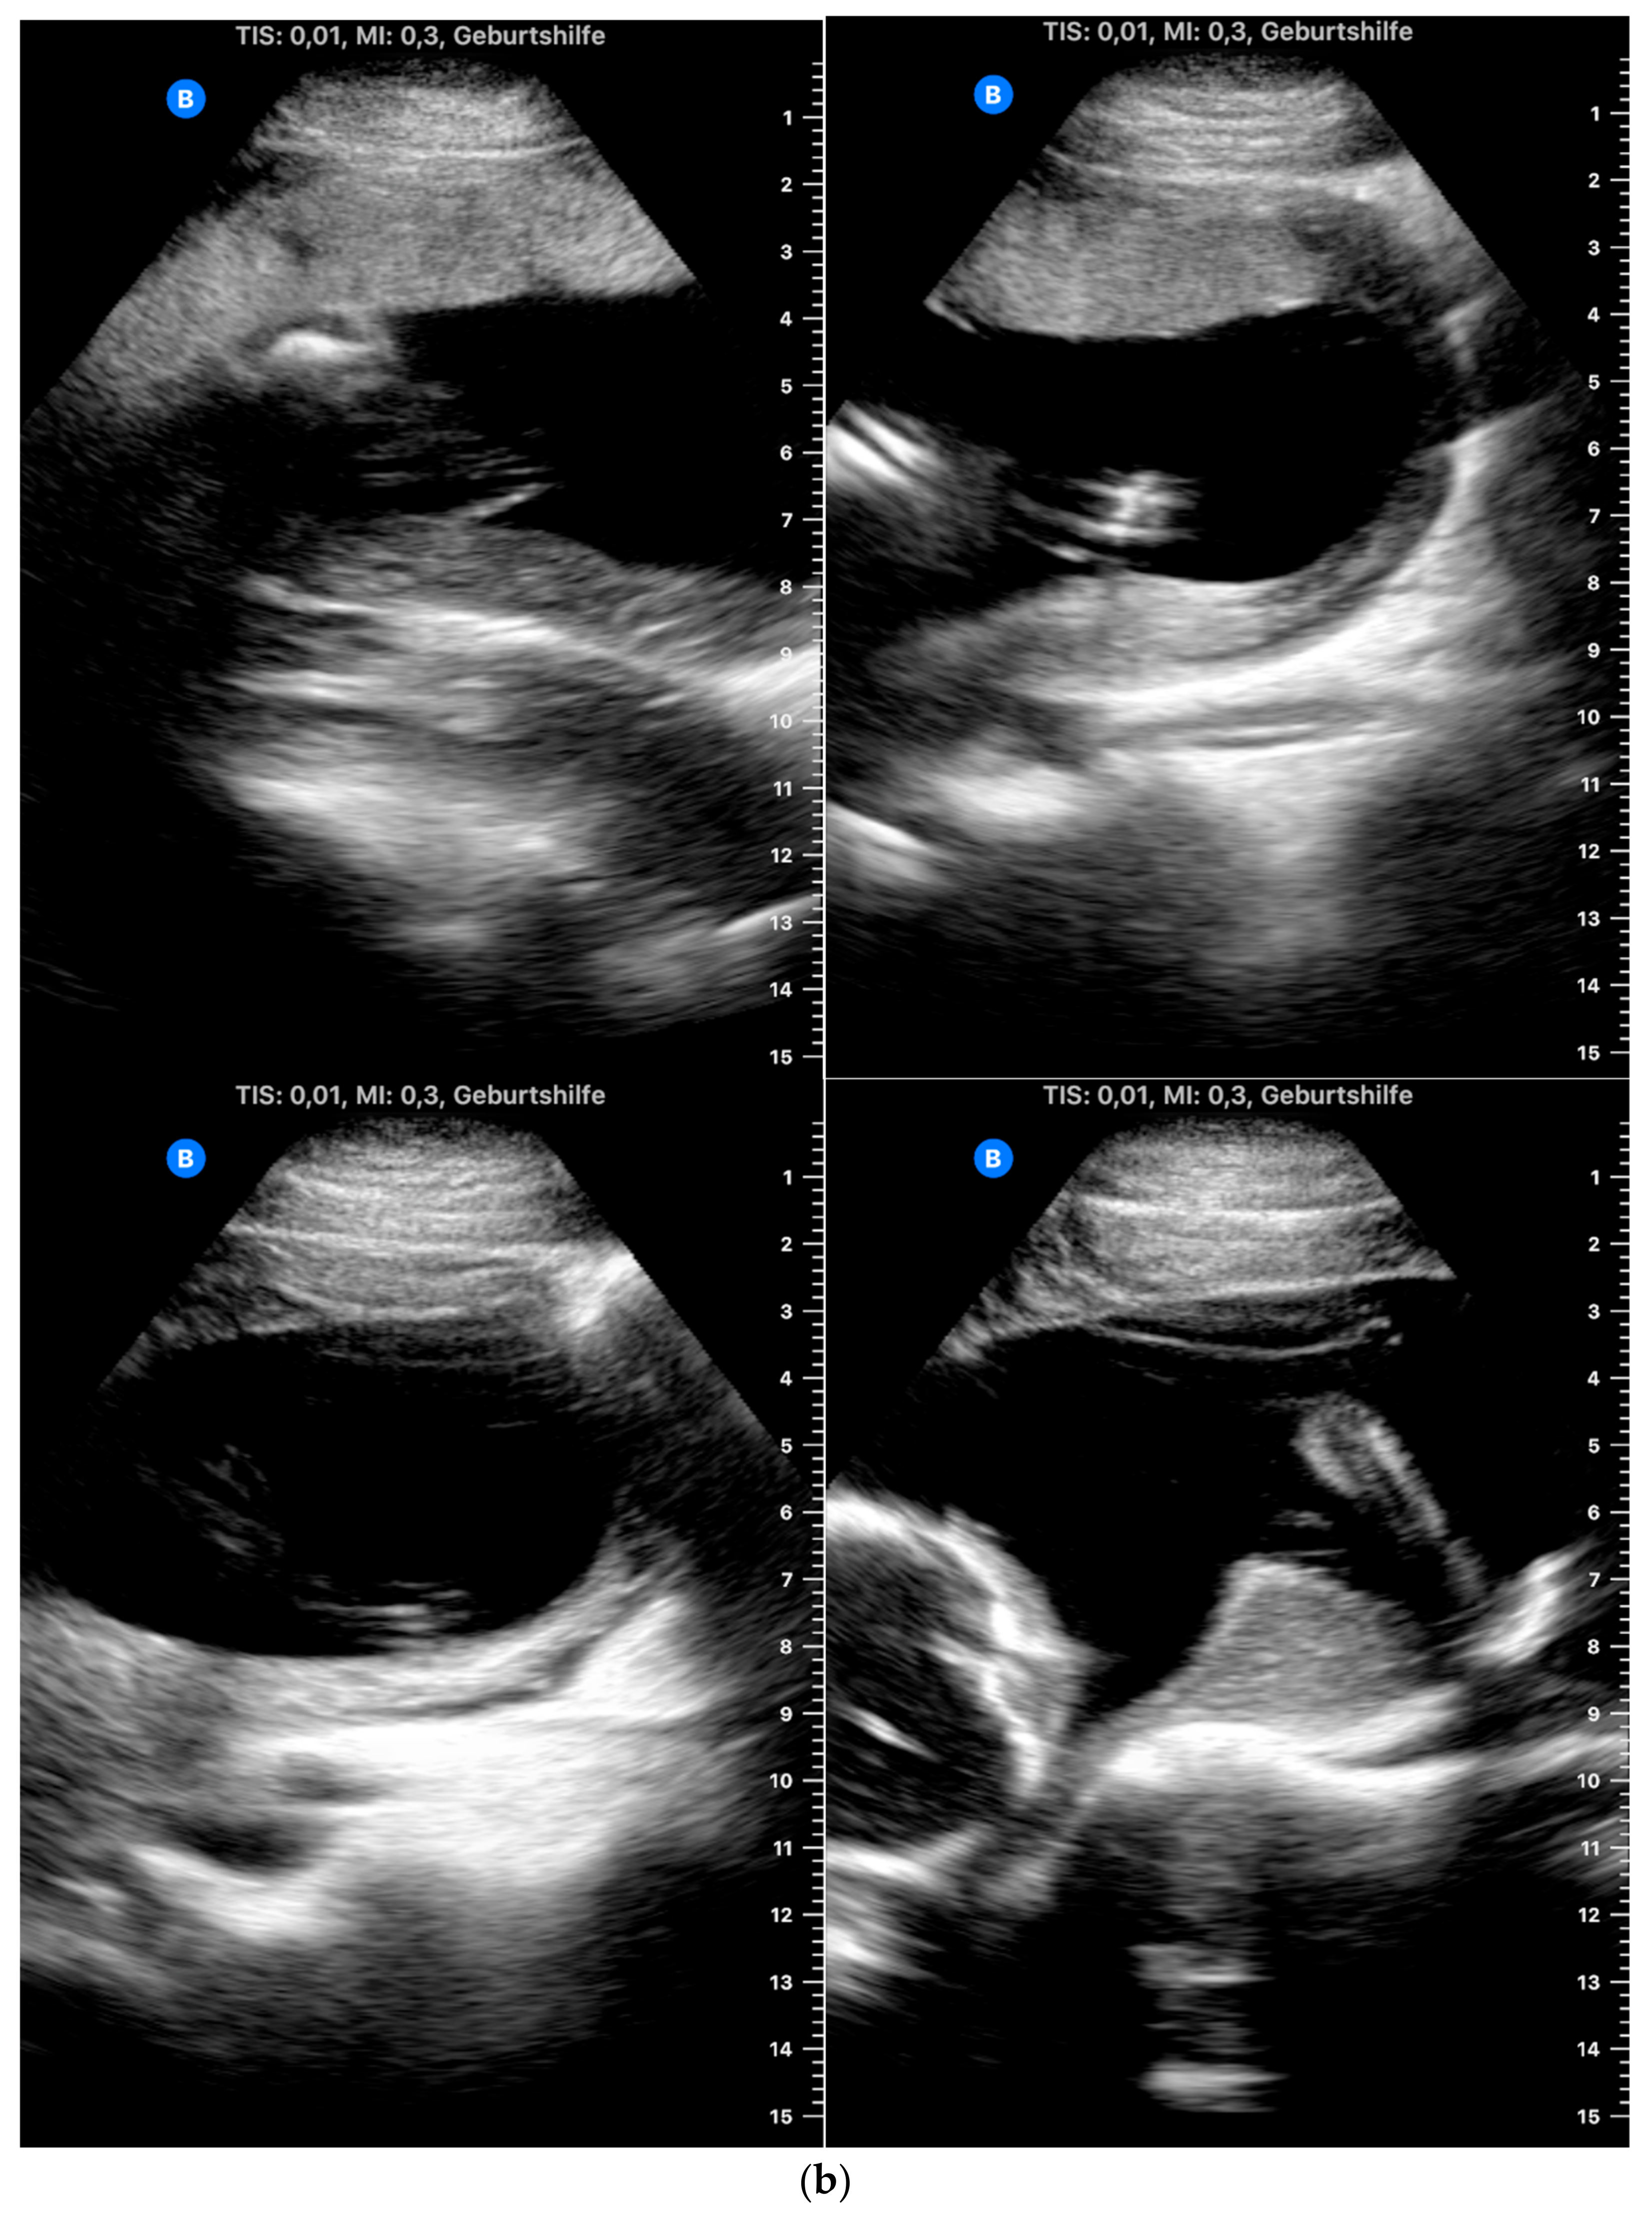

The heartbeat was correctly captured by more than half of the participants (n = 24, 52.2%; Table 3) (Figure 2a,b).

Figure 2.

(a) Example of an image obtained by a study participant in cohort A, showing the heartbeat (satisfactory presentation). (b) Example of an image obtained by a study participant in cohort B, showing the heartbeat (satisfactory presentation).

With regard to identifying the amniotic fluid during the 15-s video, 43 of the 46 participants (93.5%) managed to locate the amniotic fluid correctly in at least one of the four quadrants (Figure 3a,b). A total of 52.2% succeeded in locating the amniotic fluid in all four quadrants in the videos. In relation to capturing still images of the amniotic fluid, the rate of images with sufficient quality was lower than with the videos (80.4% with at least one adequate still image in the four quadrants and 43.5% with sufficient quality in all four quadrants).

Figure 3.

(a) Example of an image obtained by a study participant in cohort A, showing the amniotic fluid (satisfactory presentation). (b) Example of an image obtained by a study participant in cohort B, showing the amniotic fluid (satisfactory presentation).